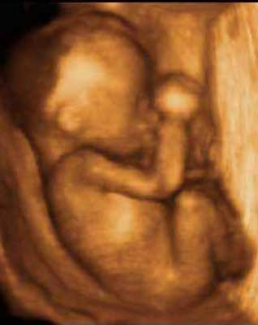

Feto de 29 Semanas Feto de 29 Semanas Feto Completo Gemelos Manos

Feto Completo